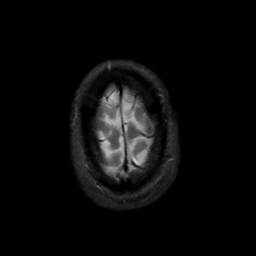

MR Study #10, April 28, 1991 -- Slice #46